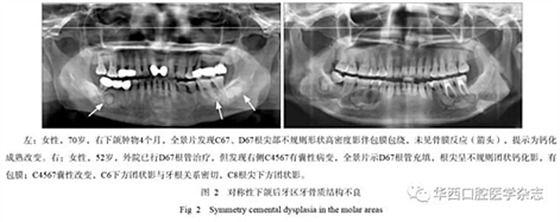

2.3 對稱性的改變

牙骨質結構不良可以呈對稱性的發(fā)生,常常發(fā)生于下頜后牙區(qū),影像學表現(xiàn)為不規(guī)則的高密度影,周圍可以有類似囊腫樣的改變(圖2),臨床醫(yī)生做完根管治療后其囊性改變并未消失,長期追蹤可能會發(fā)現(xiàn)其他改變出現(xiàn)。